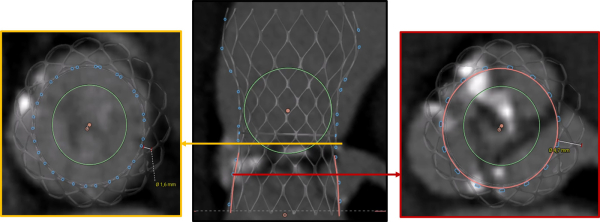

Simulation de l’implantation de l’Evolut 29

Figure 8 : gauche : Valve – Sinus < 2mm - droite : Valve – Coronaire > 4 mm